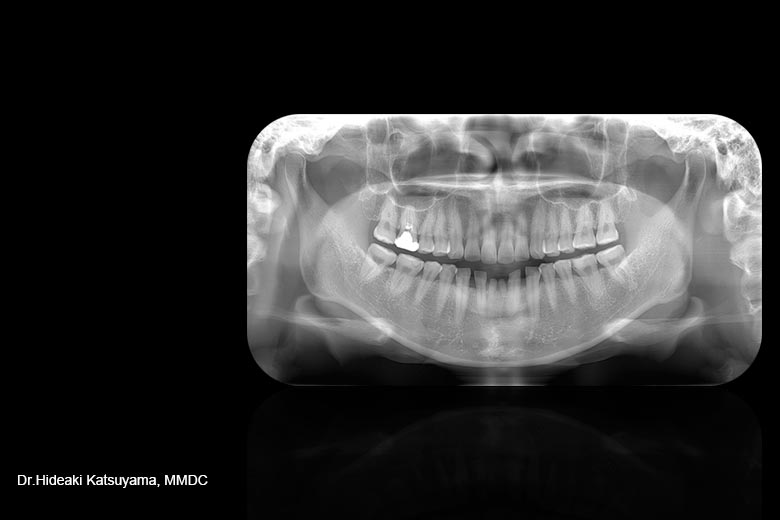

先天的に前歯が2本欠損しており、晩期残存していました下顎前歯部の審美的な改善を目的とし、インプラント治療を希望して来院されました。 先天的に前歯が2本欠損しており、晩期残存していました下顎前歯部の審美的な改善を目的とし、インプラント治療を希望して来院されました。

2本の前歯が欠損していますが、レントゲンで見る限り、下顎の前歯の歯根が近接していて、近遠心的なインプラントを入れるスペースがないことがわかります。 2本の前歯が欠損していますが、レントゲンで見る限り、下顎の前歯の歯根が近接していて、近遠心的なインプラントを入れるスペースがないことがわかります。

-

そのため、理想的な治療結果を達成するため、 そのため、理想的な治療結果を達成するため、

矯正治療を併用したインプラント治療を計画しました。